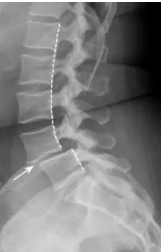

Q

Espondilolistese

* Deslizamento de uma vértebra sobre a outra

* Pode ser:

A

1. Verdadeira (lítica): decorrente de uma espondilolise

2. Falsa (degenerativa): decorrente de espondiloartrose